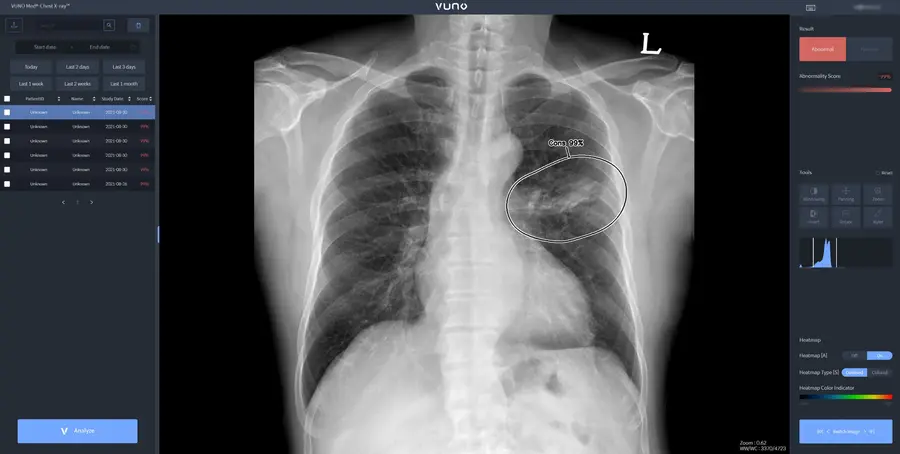

▲ '뷰노메드 체스트 엑스레이™' 스크린샷

4개 제품 중 첫 번째로 대만 허가를 획득한 뷰노메드 체스트 엑스레이™는 흉부 엑스레이 영상에서 결절, 경화, 간질성 음영, 흉수, 기흉 등 주요 이상소견을 높은 정확도로 탐지하고, 위치와 소견명을 제시해 결핵, 폐렴 등 주요 폐 질환 진단을 돕는 인공지능 솔루션이다.

해당 솔루션은 영상의학 분야 최고권위 학술지인 Radiology에 게재된 임상연구에서 높은 판독 정확도와 효율성을 입증한 바 있다. 또한 국내외 주요 중대형병원 임상현장에서 활발하고 사용되어 임상적 가치가 검증된 주요 제품 중 하나다.